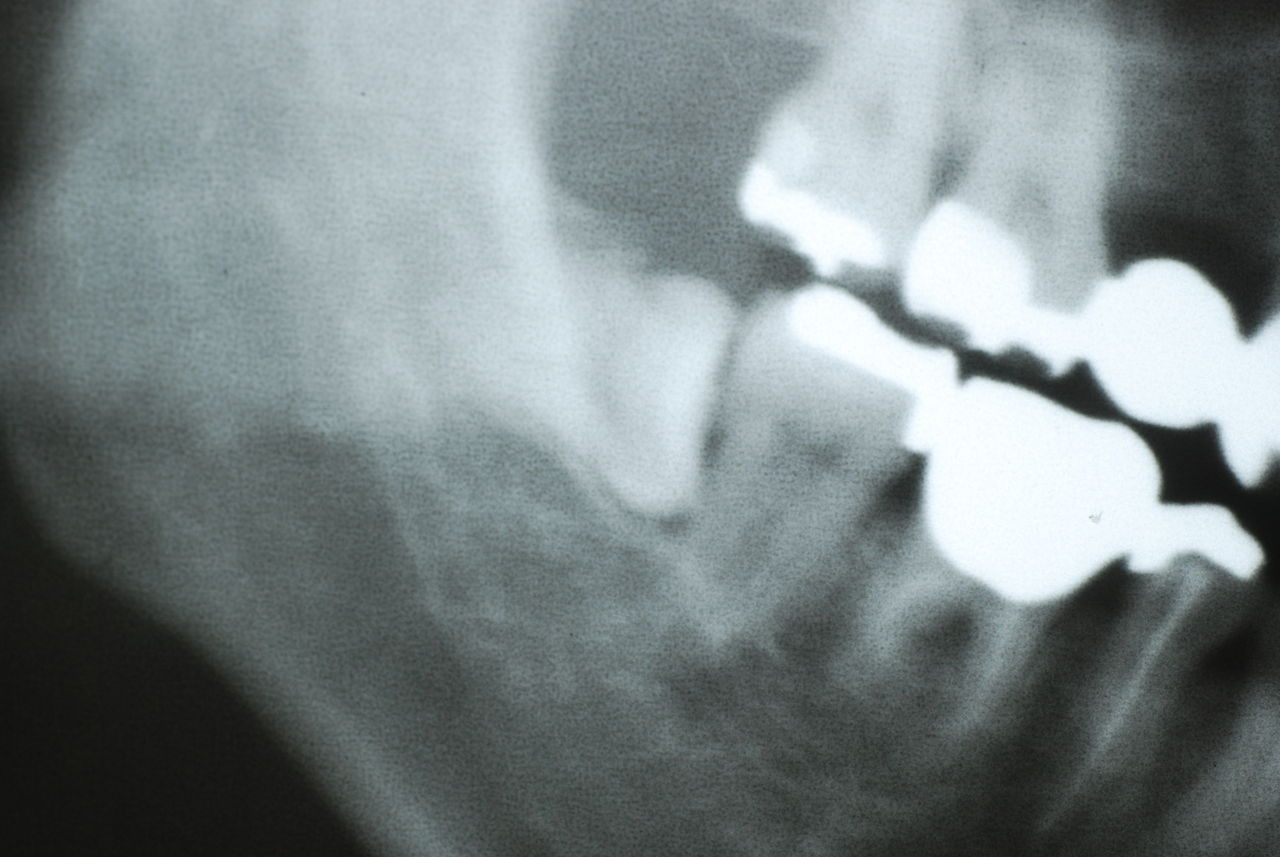

左下の歯は歯の中の治療も?ですごい歯周病を患い歯茎の穴(ポケットと呼ばれるところ)から膿が出ているのです。ばい菌と毒素で骨が溶けて深い穴ができてそこにまたバイキンと毒素がたまるという悪循環ができているのですね。